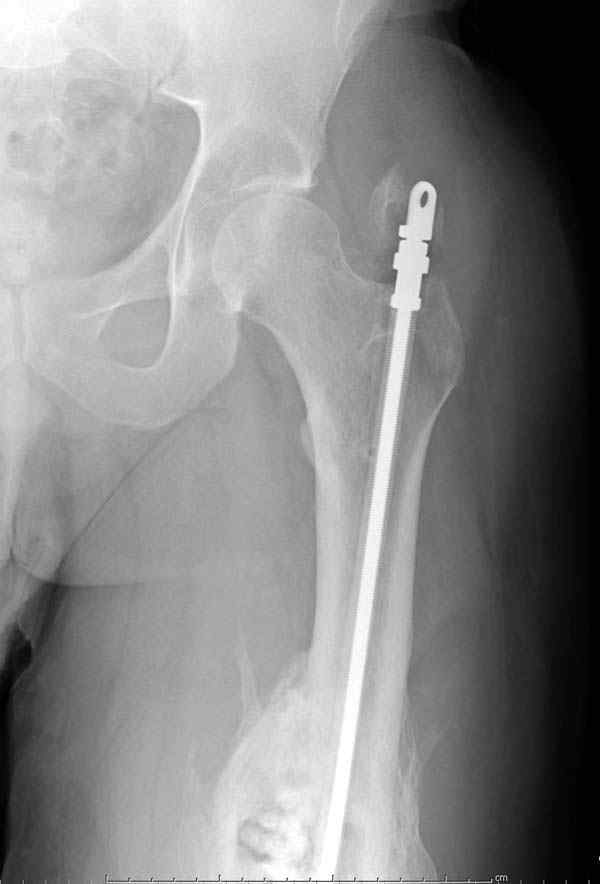

Недавний случай: год назад леченный интрамедуллярным гвоздем открытый перелом бедра инфецировался, многократные Irrigation&Debridment

закончили вставлением антибиотического гвоздя и кожной пластикой переднего мягкотканнего дефекта.

старый снтибиотический гвоздь

ренгенограмма инфицированного бедра со старым

антибиотическим гвоздем